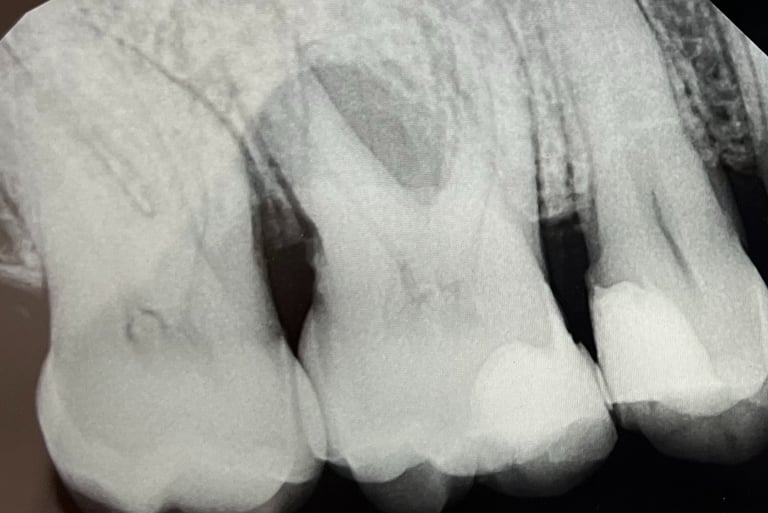

Il primo premolare superiore destro presenta una grave perdita ossea, visibile come un’area grigio scuro lungo il lato destro della radice. Le opzioni di trattamento consistono nel trattamento parodontale o estrazione del dente. A un anno dal trattamento rigenerativo parodontale, si osserva un netto miglioramento della situazione, con un evidente riempimento osseo attorno alla radice nella zona precedentemente compromessa.